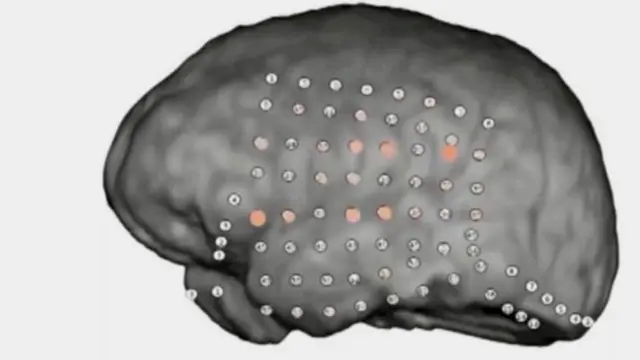

وتمكن قائد فريق البحث كريستوفر هولدغراف، من جامعة كاليفورنيا، ورفاقه من العمل مع مرضى الصرع، والذين خضعوا لإزالة جزء من الجمجمة ووضع أقطاب كهربائية على سطح الدماغ لتتبع نوبات مرضهم.

صدر الصورة، UC BERKELEY

وخضع سبعة أشخاص للاختبار السمعي الذي أجراه العلماء.

وأظهرت تسجيلات الدماغ لحظة التعرف على معنى الجملة، وأنماط نشاط الدماغ في المناطق المعروفة بارتباطها بعملية معالجة الصوت وفهم الكلام.

وكشف الباحثون عن رصد نشاط بسيط في تلك المناطق بأدمغة عينة البحث، عند سماع جملة مشوشة.

لكن عند سماع جملة مفهومة بشكل واضح كان هناك أنماط نشاط أكبر في تلك المناطق في الدماغ.

عندها "أضاءت" مناطق معالجة الكلام والسمع وتغير نمط نشاطها مع مرور الوقت، وتم رصد الكلمات بوضوح من بين الضوضاء.